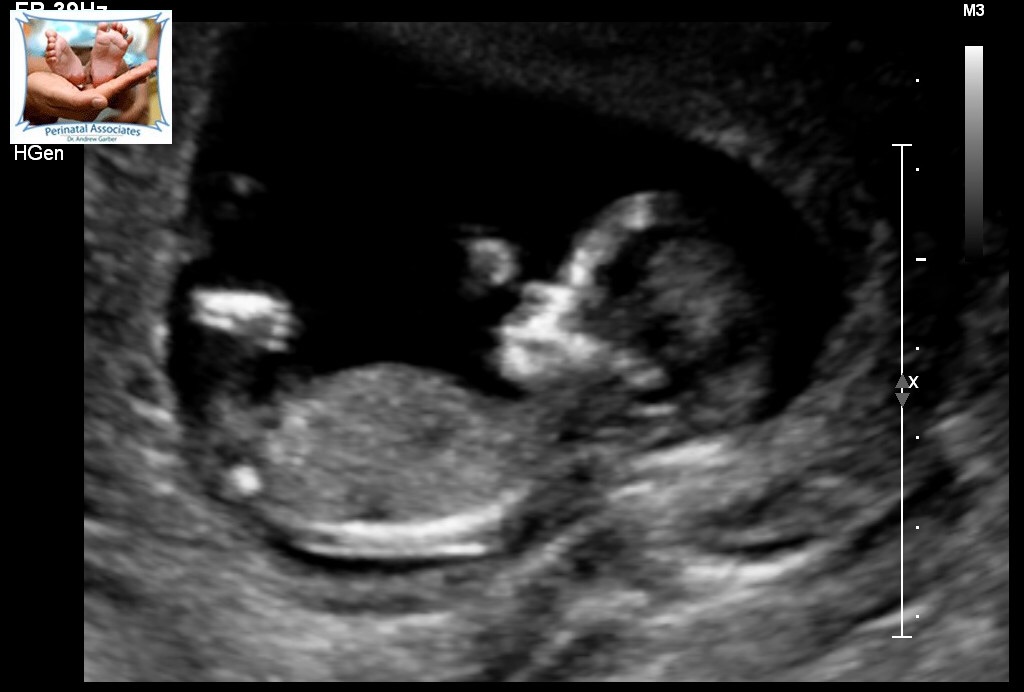

This is from 13 weeks. Can anyone guess what gender? The tech could not find a penis or nub like thing (looked for 30 minutes) and determined she is not convinced about it being a boy but could not exactly see the girl parts.Attachment 26141Attachment 26142Attachment 26143Attachment 26144